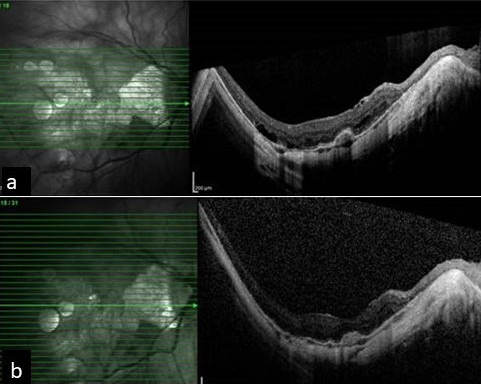

The sequence of events in six years of a myopic traction maculopathy.

Methods: Our female patient who is a high myope developed myopic choroidal neovascular membrane (CNVM), for which she received three anti-vascular endothelial growth factor injections (VEGF). It was scarred for a while. Later she developed myopic foveoschisis with macular detachment which progressed over a period with deterioration of vision.

Results: She underwent pars plana vitrectomy with silicone oil tamponade. Oil removal was done eight months later. At the last follow up visit, her macula was flat with stable vision.